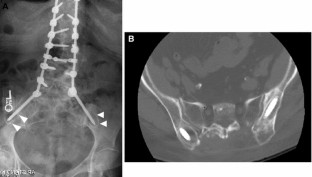

Sacropelvic fixation should be considered in any patient with a long construct ending in the sacrum, those patients with associated risk factors for loss of distal fixation or high risk for pseudarthrosis at L5–S1, and those undergoing three column osteotomies or vertebral body resections in the low lumbar spine. Current pelvic fixation techniques with iliac screws, multiple screw/rod constructs, and S2-alar-iliac screws are all viable techniques for achieving pelvic fixation.

There is growing evidence that pelvic fixation may become the standard for obtaining long fusions in adult scoliosis. Although technically challenging, in selected cases the use of four pelvic screws and/or four rods across the lumbosacral pelvis can help address pseudarthroses, implant breakage, and screw pullout secondary to osteoporosis. Ultimately, indications and techniques should be individualized to the patient and based on surgeon preference and experience.